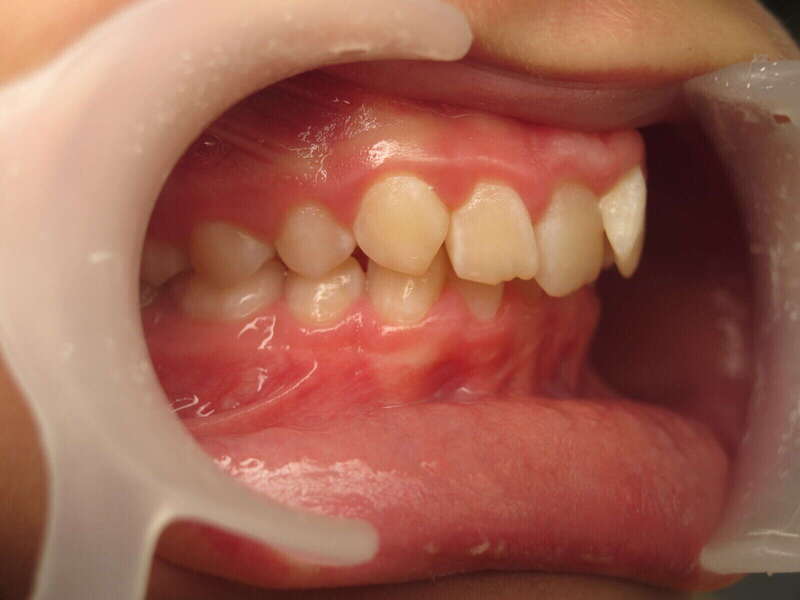

Cas n°1 traité par aligneurs (interception) - enfant

Ce cas d’interception chez un enfant de 8 ans démontre l'efficacité des aligneurs pour corriger des troubles fonctionnels précoces. Le diagnostic présentait des inversions d'articulé provoquant une déviation de la mandibule vers la gauche et un décalage des milieux.

Grâce à une coopération exemplaire et un traitement totalement indolore, l'expansion de l'arcade a permis de recentrer la mâchoire. Cette intervention a littéralement remis la croissance sur les rails, neutralisant le risque d'asymétrie faciale squelettique.

Avant

Après